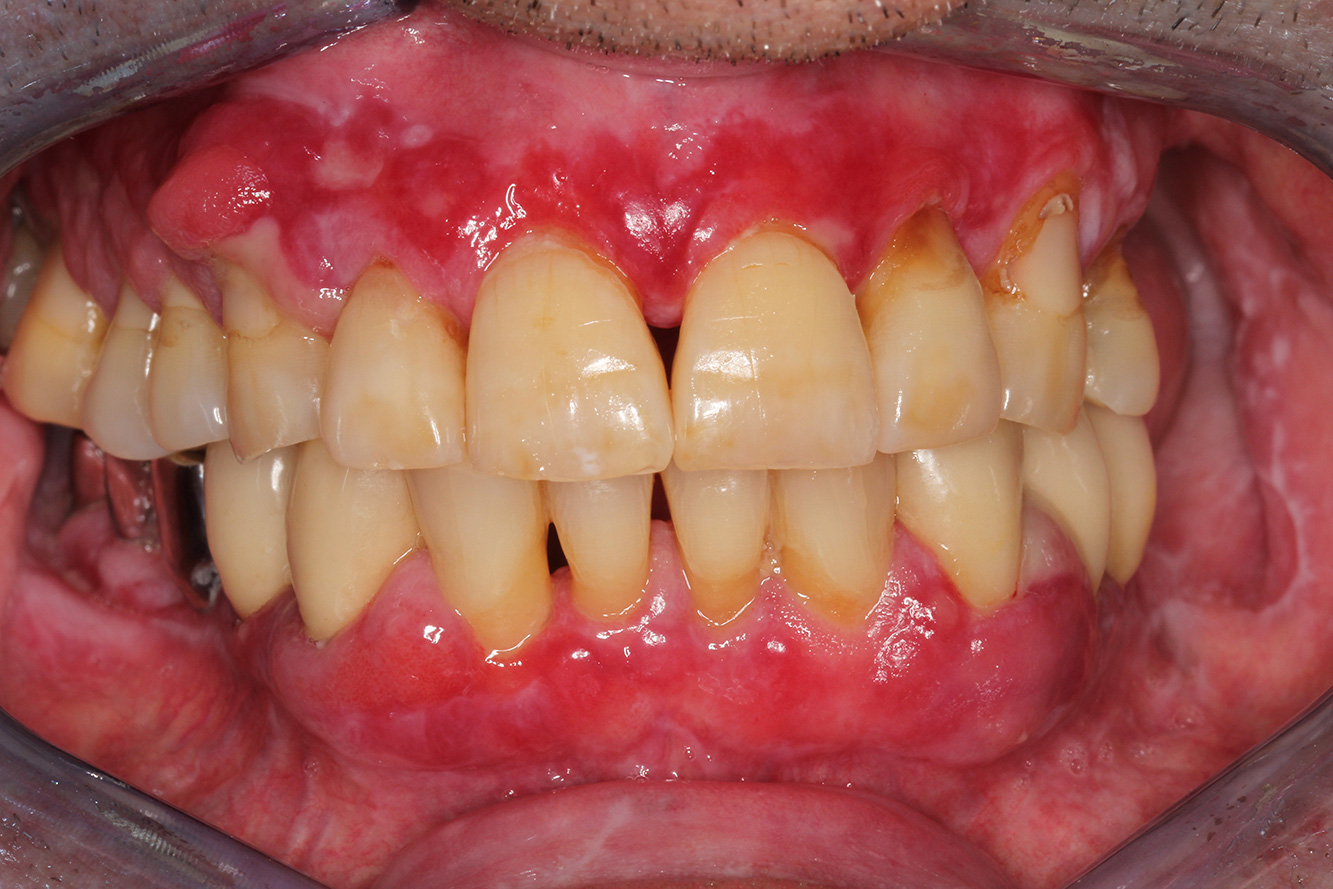

Ein 71-jähriger Patient mit Z.n. Nierentransplantation und Hypertonie (Bluthochdruck) stellt sich vor. Bedingt durch die Krankengeschichte ist eine Dauermedikation mit Cyclosporin, zur Unterdrückung der Immunabwehr, und Amlodipin, zur Blutdrucksenkung, erforderlich. Außerdem berichtet der Patient über empfindliches Zahnfleisch und Zahnfleischbluten. Aus mundgesundheitlicher Sicht zeigt sich ein saniertes Gebiss mit acht fehlenden Zähnen, ausgeprägte Gingivawucherungen, eine Parodontitis Stadium II, Grad B mit aktiven Taschen und eine initiale Wurzelkaries an Zahn 22. In der Kariesrisikoabschätzung wird ein mittleres Kariesrisiko (API 60) festgestellt. Für die Prophylaxesitzung lassen sich folgende Behandlungsempfehlungen ableiten.

Anhand der Krankengeschichte lässt sich ein besonderes Komplikationsrisiko erkennen. Aufgrund des Nierentransplantats ist der Patient immunsupprimiert (Cyclosporin), verfügt also über ein geschwächtes Immunsystem und benötigt eine Infektionsprophylaxe (Empfehlung: 2 g Amoxicillin als Antibiotikum 1h vor Sitzung). Gleichzeitig birgt die Dauermedikation des Patienten ein erhöhtes Erkrankungsrisiko, da die festgestellten Gingivawucherungen medikamentenassoziiert sind (20).

Besonders im Bereich der Motivation und Instruktion muss auf die Situation des Patienten eingegangen werden. Durch die Gingivawucherungen gestaltet sich die häusliche Mundhygiene schwierig. Die erhöhte Anfälligkeit für Infektionen sowie das Fortschreiten und die Neuentstehung der Wucherungen (22) sollte auf Augenhöhe thematisiert werden. Gleichzeitig müssen die individuell auf den Bedarf abgestimmten Hygienetechniken vermittelt werden.